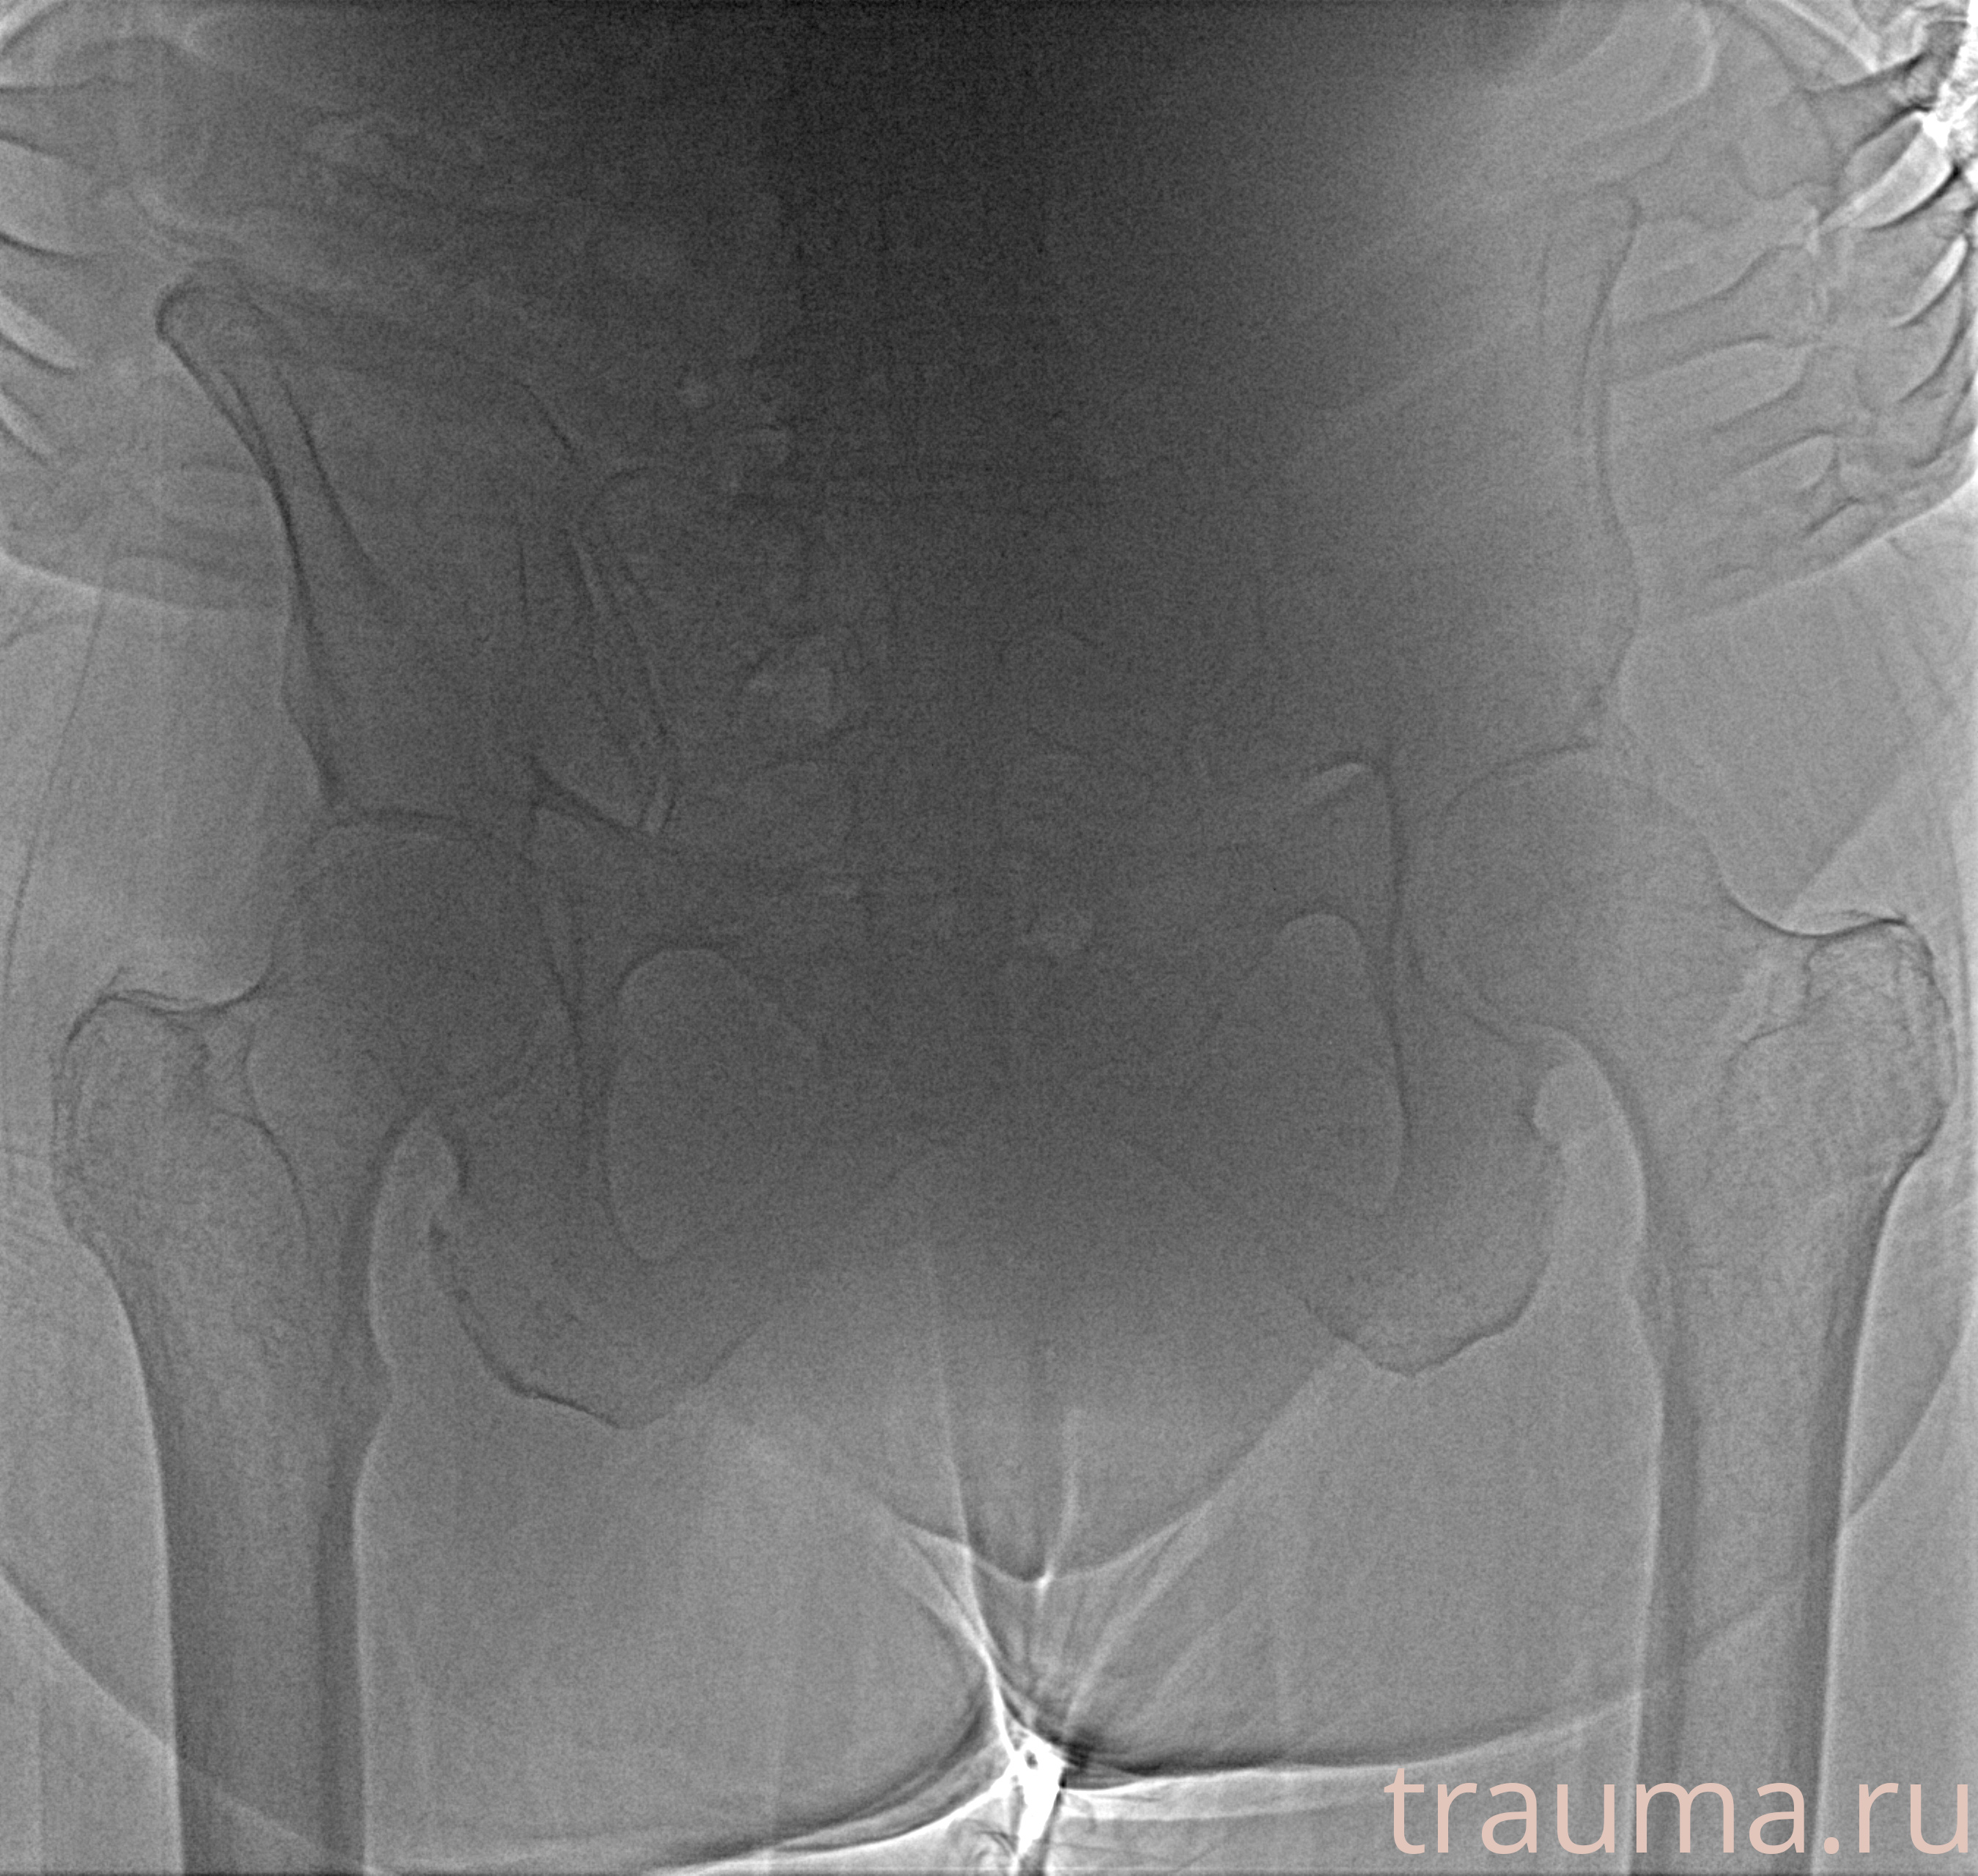

Рентген на дому: по вашему адресу приезжает врач-рентгенолог, травматолог-ортопед с мобильным рентгеновским аппаратом, проводит диагностику травмы или заболевания, делает необходимые рентгенограммы, дает рекомендации по дальнейшему лечению. Получить качественные снимки в домашних условиях возможно благодаря уникальной методике, разработанной МосРентген Центром для института  Склифосовского